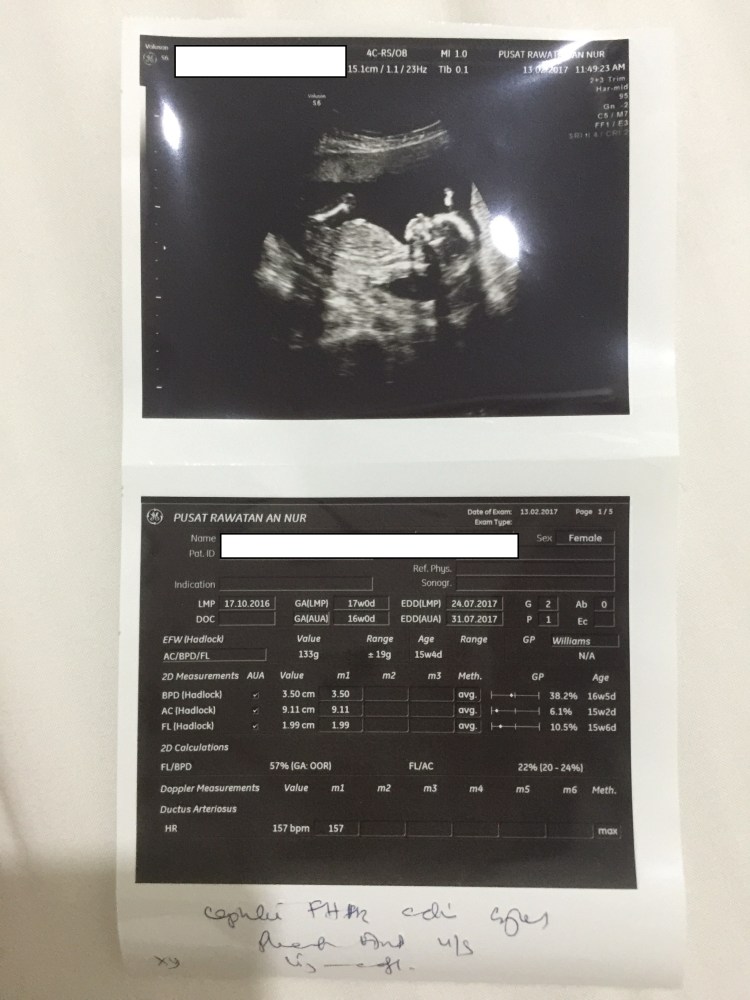

[Updated March 13,2017]

- Scan 2D

- Alhamdulillah sudah memasuki minggu 16/17 kamdungan.

- Memeriksa di Poliklinik An Nur di Batu Berendam untuk 2D scan pada 13 feb.